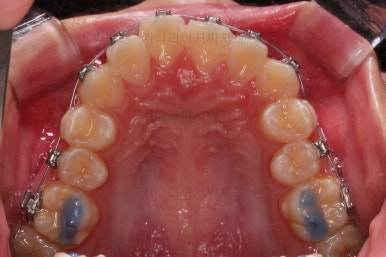

부산덧니교정 마무리를 한 모습인데요.

가지런한 모습 좋고, 교합이나 중앙선 등 매우 잘 맞네요.

전후를 비교해 볼게요.

치열, 교합, 악궁의 형태 매우 좋아졌어요.